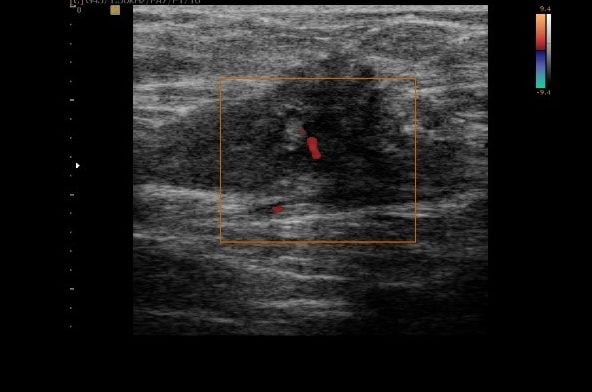

dor na cicatriz da cesárea

Endometriose na cicatriz da cesárea, identificada em um exame de ultrassonografia. Identifica-se na imagem um nódulo escuro e pouco vascularizado.